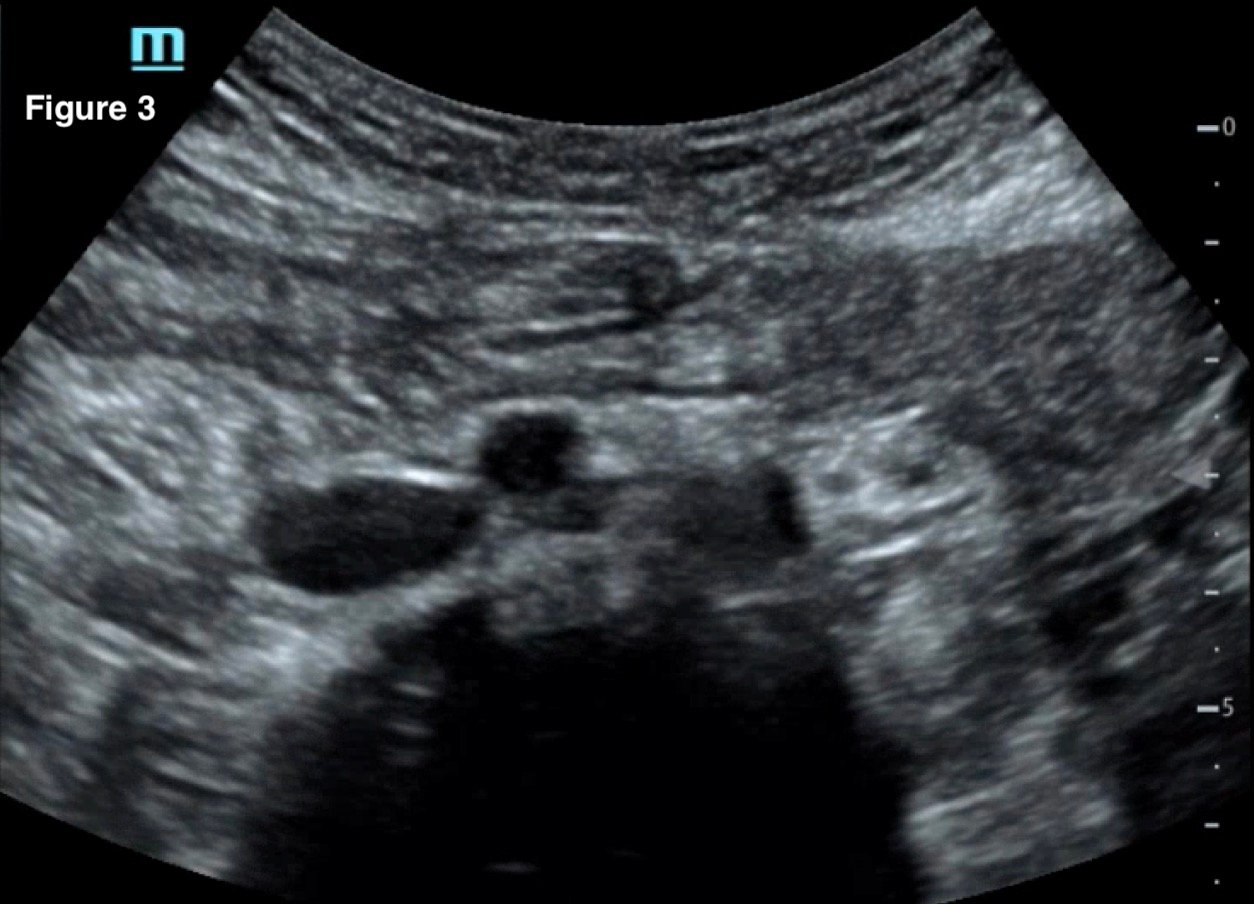

May-Thurner syndrome (MTS) is most commonly caused by the compression of the left iliac vein by the right iliac artery against the lumbar spine, which leads to the development of a partial or occlusive deep venous thrombosis (DVT).1 Diagnosis begins with a duplex ultrasound of the lower extremities to evaluate for a femoropopliteal thrombus, and in high-risk patients where a more proximal DVT is suspected and the DVT ultrasound is negative, a computed tomography venogram (CTV) or magnetic resonance venogram (MRV) is performed.1,3 In this case report, a patient presented to the emergency department (ED) with two days of left lower extremity pain and swelling. Initial lower extremity DVT ultrasound was negative, so a CTV was ordered and revealed a thrombus in the left common iliac vein with overlying compression by the right common iliac artery, suggesting the diagnosis of May-Thurner syndrome (Figure 1). Afterwards, a point-of-care ultrasound (POCUS) was performed at bedside to evaluate the caval and iliac arteries and the findings were consistent with the CTV (Figure 2, 3, 4). If the POCUS was performed prior to the CTV, the patient may have been spared the radiation exposure from CT, as well as the risks of intravenous (IV) contrast required for a venogram. Therefore, in high risk patients in whom a negative DVT ultrasound will prompt advanced imaging with CTV or MRV, I propose the addition of a lower abdominal ultrasound using a curvilinear probe to assess the caval and iliac arteries prior to obtaining a CTV or MRV.